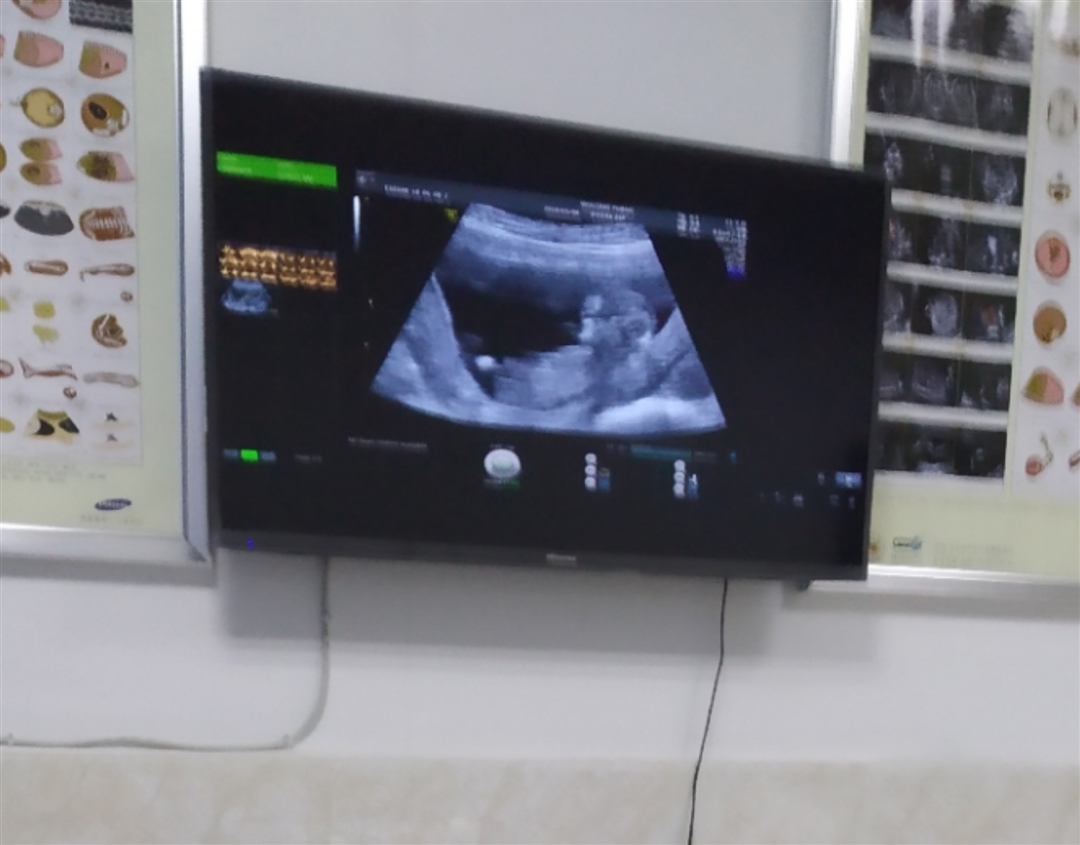

孕11周+2天

哼唧猪宝宝[帖主]:传你好孕( ^_^)/

哼唧猪宝宝[帖主]:NT检查是对12周胎儿颈部透明层厚度的监测,筛查早期畸形。妊娠11周之前胎儿过小,透明膜的透明层的厚度测量误差较大,14周之后胎儿颈部脂肪增厚,会增加测量误差。因此建议在11-13周加6天进行NT检查。若胎儿颈部透明层厚度>2.5mm,甚至超过3-3.5mm以上,提示胎儿有畸形的可能

哼唧猪宝宝[帖主]:不是,类似腹部b超